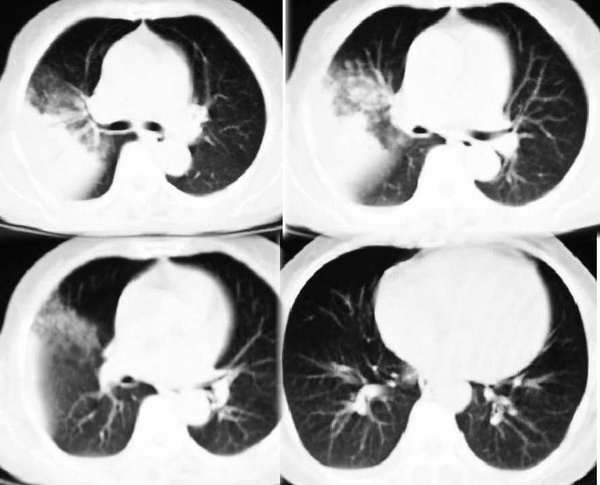

右上叶后段见大片状实变阴影,见含气支气管征,近肺门见支气管血管束增粗,上腔静脉后见小淋巴结. 后胸膜腔见少量积液. 印象:1,大叶性肺炎.2,节段性肺炎<混合菌感染>.3.建议抗炎后复查待除外其他病变

应该是大叶性肺炎,下袁平直,且见空气支气管,分支清楚,没有枯树枝那种改变

右肺大片状阴影,边缘模糊,其内见充气支气管征,首先考虑大叶性肺炎,抗炎治疗的同时再做一个痰培养排除浸润性结核吧

右肺上叶肺实变,内见①支气管气像②边缘模糊③叶间裂稍饱满这些都是支持肺炎的证据。尤其是边缘模糊,其病理学依据是炎症渗出性物质通过肺泡间孔和/或呼吸性细支气管向临近的肺组织蔓延渗透,和其他表现在一起成为诊断肺炎的重要表现。

大叶性肺炎,右侧少量反应性胸水